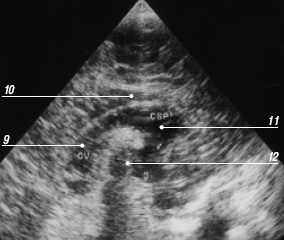

Прозрачная перегородка узи

Прозрачная перегородка узи 109 фотографий